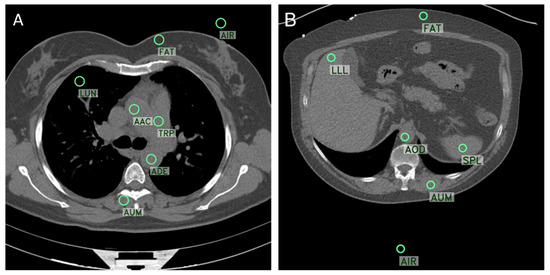

2.2. Objective Image Quality Analysis